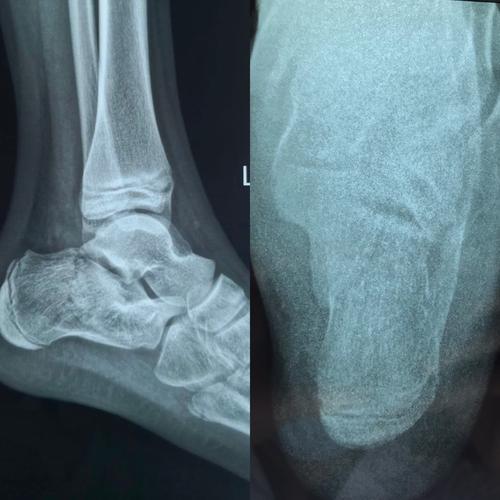

x线跟骨轴位的最佳投照方法以及对跟骨骨折临床诊断的价值.doc

青海省康乐医院骨科带您了解跟骨骨折

男42岁,跟骨骨折